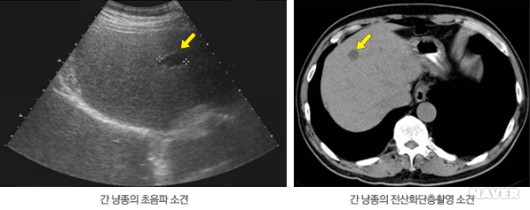

신체 진찰로는 진단할 수 없고, 복부 초음파 검사나 CT, MRI 등의 영상검사로 진단한다. 간낭종은 그 자체로는 임상적 의의가 없으나 다른 낭종성 병변과 감별이 중요하다. 한 가지 영상 검사만으로도 충분히 진단이 가능하여 일반적으로는 정밀 검사를 요하지 않으나, 드물게 농양의 가능성이 있거나 낭선종(cystadenoma)나 낭선암(cystadenocarcinoma)과의 감별이 필요할 경우에는 CT나 MRI 등 추가 검사가 필요할 수도 있다.

간 낭종 진단